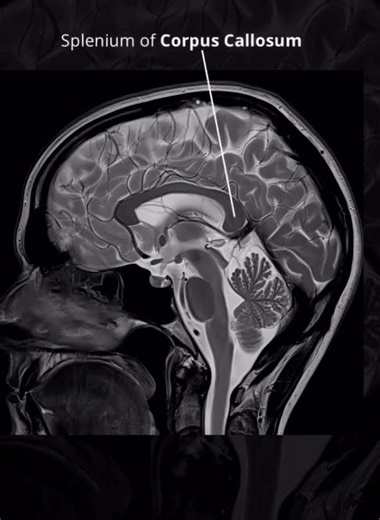

Software - MRI

MRI 3D - 3D Printer Slicer

Download - TMJ MRI

Anatomy - Qidi 3D Slicer